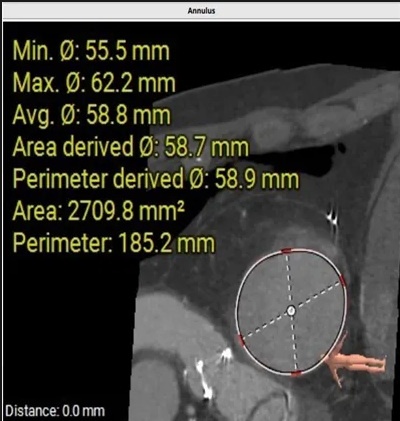

術(shù)前心臟CT評估

三尖瓣環(huán)平均周長徑58.8mm,最大直徑62.2mm